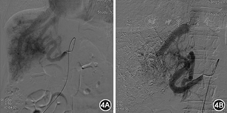

入院后经会诊于2014年12月3日行冠状动脉造影未见明显狭窄。右心导管术:外周血氧饱和度100%,上腔静脉氧71%,主肺动脉氧84%,右心房氧83%,右心室氧84%,右心室射血分数59%,肺动脉楔压15 mmHg,心输出量11.8 L/min(成年人正常值5~6 L/min),心脏指数7.7 L·min-1·m-2(成年人正常值3.0~3.5 L·min-1·m-2),左向右分流比率1.8(正常值为1.0)。鉴于患者上腔静脉和右心房血液氧饱和度相差大,且心脏指数、左向右分流比率均增高,需寻找左向右的异常分流的部位。因当时未测量下腔静脉血氧饱和度,超声与胸部血管CT检查均未发现有房室间隔缺损及异位肺静脉引流,故疑有下腔静脉异位引流。2015年4月20日上腹部血管CT未见明显粗大的肝动脉肝静脉直接相通征象,但动脉期肝静脉即显影,肝动脉及肝静脉异常增粗,符合肝动脉-肝静脉瘘(hepatic arteriovenous fistula, HAVF)(图1,图2)。经股动脉行肝血管造影见肝左动脉起自胃左动脉,胃左动脉及肝总动脉明显增粗,扭曲明显,动脉期可见肝静脉提早显影,肝内见弥漫性HAVF,以肝右动脉肝静脉瘘为主,由肝固有动脉、肝左动脉及右膈动脉供血。用无水酒精和适量明胶海绵颗粒制成的乳剂栓塞肝右动脉分支,栓塞后造影见肝右叶HAVF大部消失(图3)。术后患者偶感胸闷心悸明显,劳累后加剧,于2015年6月30日复查肝血管造影见双侧膈动脉和肝总动脉均增粗、扭曲,仍有弥漫性HAVF,由肝动脉及膈动脉供血,肠系膜上动脉造影见动脉盗血现象(图4)。分别采用浓度为25%和28%的正丁基-2-氰基丙烯酸盐进行栓塞肝右动脉两个分支,栓塞后肝右动脉肝静脉瘘消失,肝左动脉还存在动静脉分流,术后胸闷心悸症状好转。术后半年复查超声心动图示左、右心房较前明显缩小:LVEF 71%,LAD 38 mm,RAD 31 mm,LVDd 54 mm,RVDd 33 mm,肺动脉收缩压33 mmHg。术后1年复查腹部血管CT:肝动静脉瘘未见明显进展,心电图在正常范围内,胸片心影较术前缩小,心胸比0.62。在1年的随访中患者未诉明显胸闷心悸不适,稍有右上腹间断性疼痛不适,口服止痛药有效,现已很少服用。